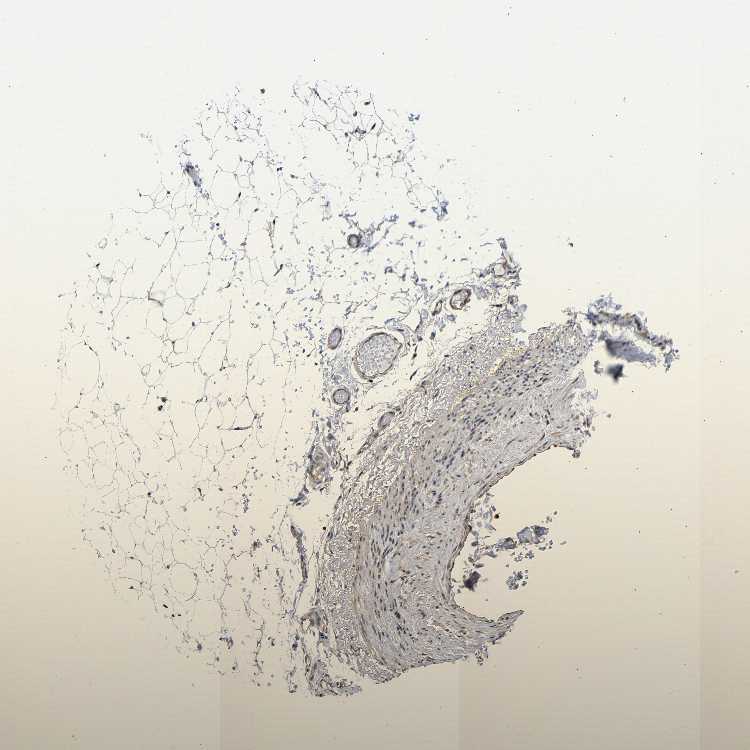

SOFT TISSUE 1 - Antibody stainingi

Antibody staining in the annotated cell types in the current human tissue is reported as not detected, low, medium, or high, based on conventional immunohistochemistry profiling in selected tissues. This score is based on the combination of the staining intensity and fraction of stained cells.

Each image is clickable and will lead to virtual microscopy that enables deeper exploration of all samples and also displays staining intensity scores, fraction scores and subcellular localization as well as patient and tissue information for each sample.

Antibody HPA012893

Fibroblasts Low

Peripheral nerve Medium